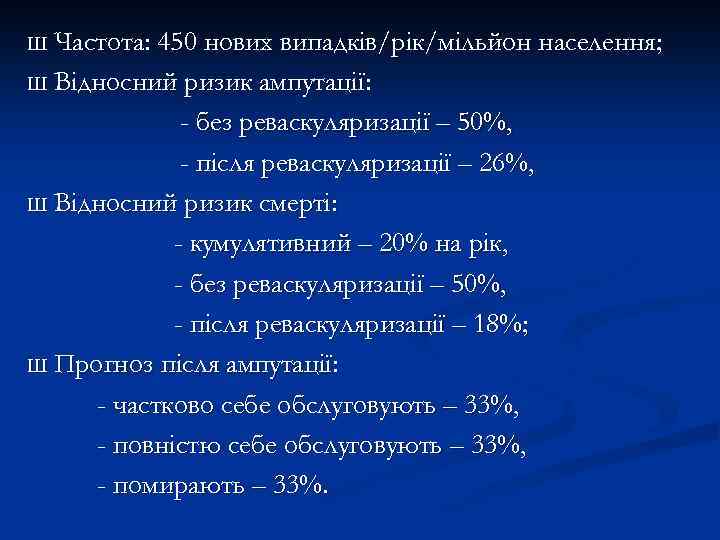

Ш Частота: 450 нових випадків/рік/мільйон населення; Ш Відносний ризик ампутації: - без реваскуляризації – 50%, - після реваскуляризації – 26%, Ш Відносний ризик смерті: - кумулятивний – 20% на рік, - без реваскуляризації – 50%, - після реваскуляризації – 18%; Ш Прогноз після ампутації: - частково себе обслуговують – 33%, - повністю себе обслуговують – 33%, - помирають – 33%.

Ш Частота: 450 нових випадків/рік/мільйон населення; Ш Відносний ризик ампутації: - без реваскуляризації – 50%, - після реваскуляризації – 26%, Ш Відносний ризик смерті: - кумулятивний – 20% на рік, - без реваскуляризації – 50%, - після реваскуляризації – 18%; Ш Прогноз після ампутації: - частково себе обслуговують – 33%, - повністю себе обслуговують – 33%, - помирають – 33%.